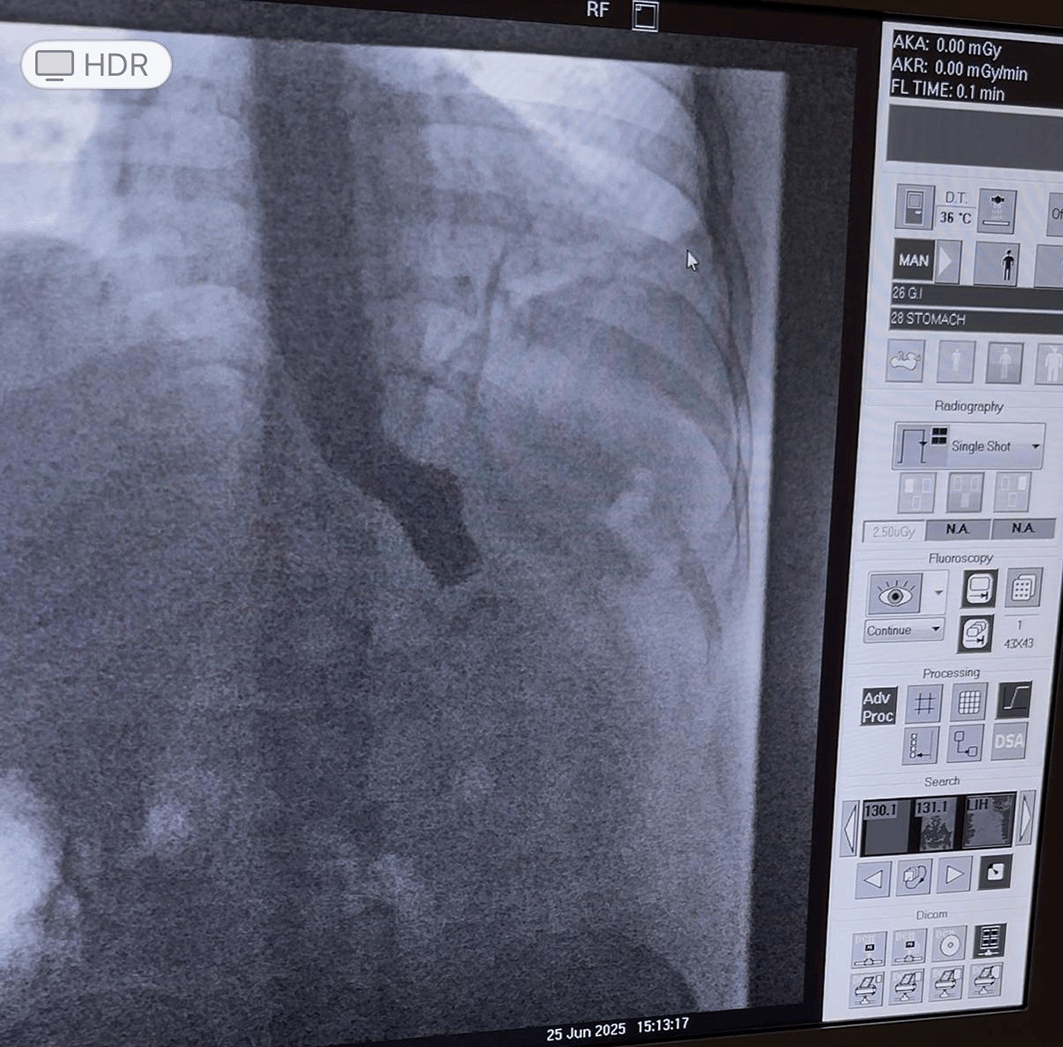

At 2:00 pm, the patient was transferred to the ward. At 4:00 pm, in the presence of the attending physician, he was allowed to drink water in small sips without dysphagia. At 9:13 pm, the patient reported a single episode of vomiting, after which no further complaints were noted. At 7:30 am the following day, the patient began to report belching and was treated with 2 ml of cerulin intramuscularly. Given persistent complaints, an abdominal ultrasound and an X-ray of the esophagus and stomach were performed at 10:30 am. Radiological assessment demonstrated obstruction at the anastomotic site ( Figure 1). Video gastroduodenoscopy confirmed anastomositis, and conservative therapy was initiated.

Figure 1. X-ray with contrast demonstrating anastomotic obstruction.